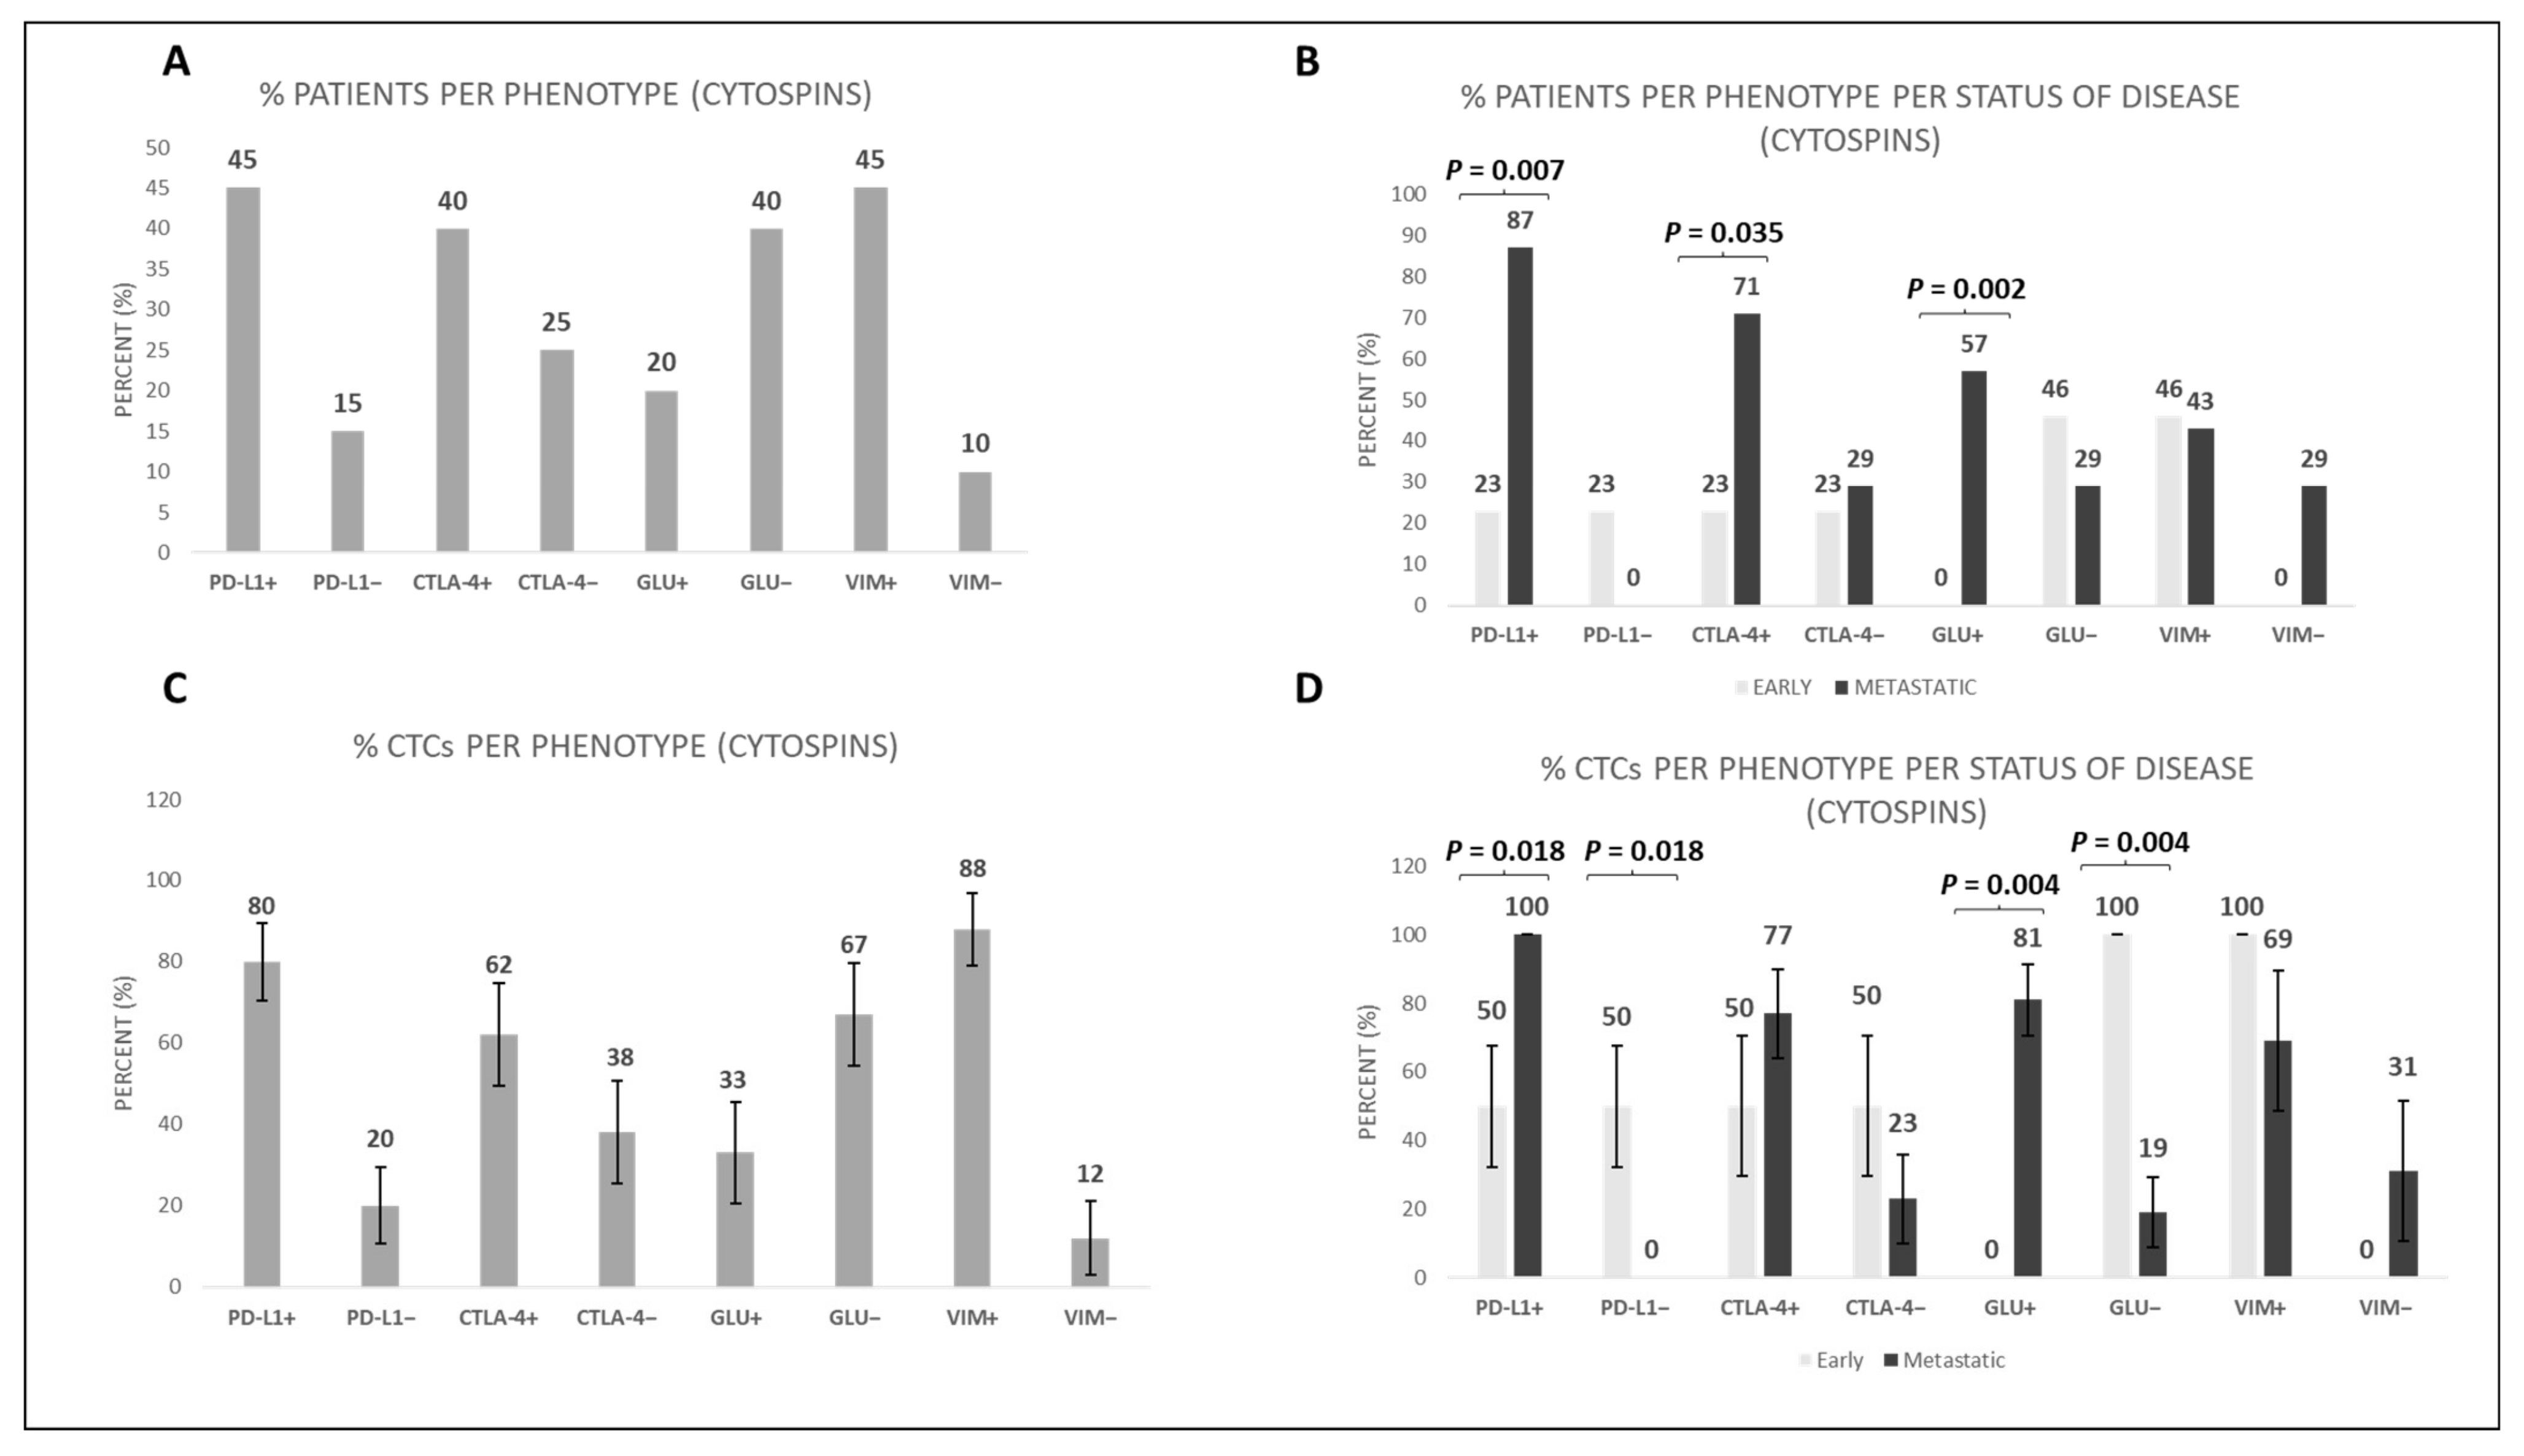

3.3. Characterization of CTCs in Cytospins and in TetherChips